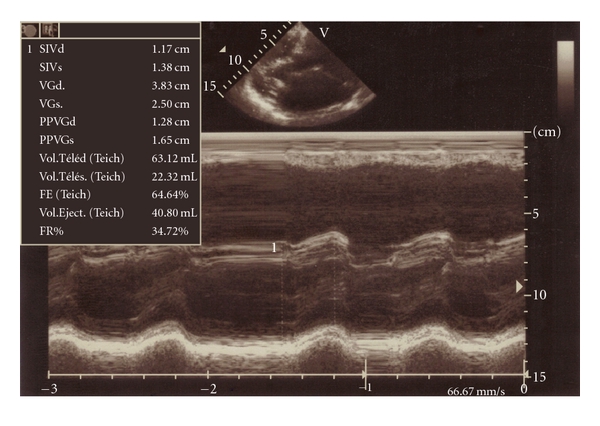

The left atrial diameter was 66.4 mm (44.3 mm/m²) (Figure 4(a)) without any thrombus. The mitral valve was thickened with a hockey stick appearance in M mode—Figure 4(b). The planimetered mitral valve area was 1.06 cm² (0.7 cm²/m²) and 0.97 cm² (0.64 cm²/m²) by pressure half-time technique. The mean left atrium-left ventricular diastolic gradient was 7 mm Hg, and the maximal one was 9.9 mm Hg. The left ventricular size was normal (25.5 cm/m²) with a paradoxical septal motion. The ejection fraction was 64% (Figure 4(c)).